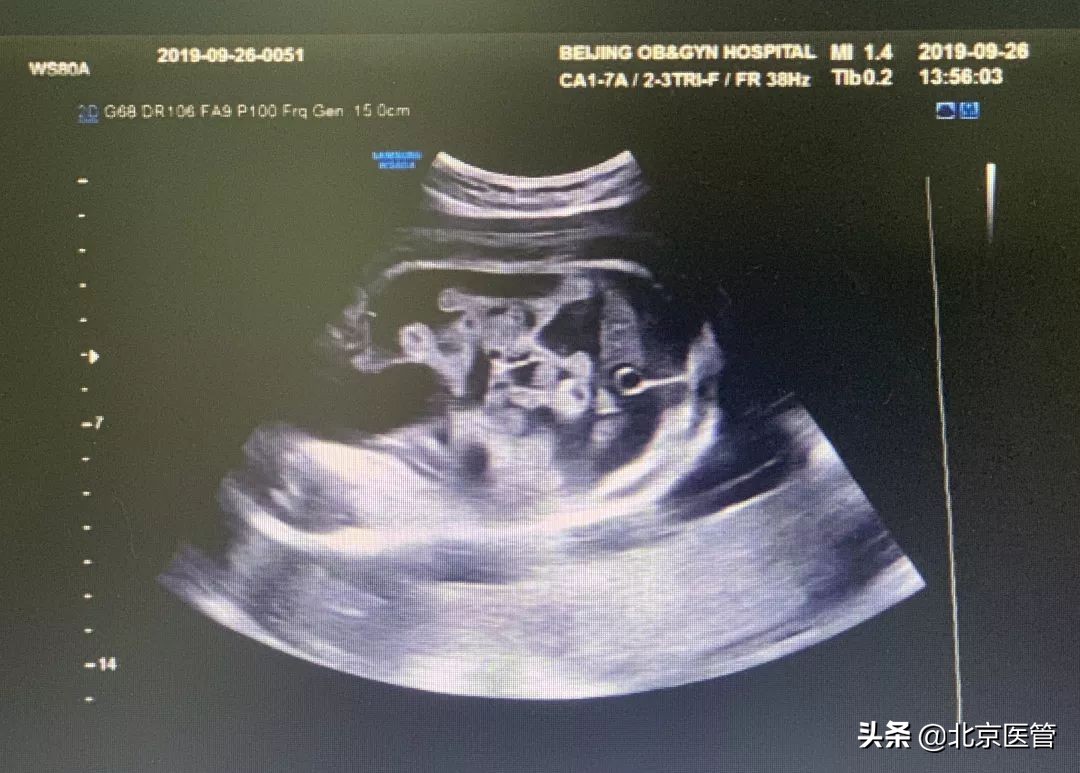

杨女士的B超提示:胎儿腹腔内可见液性暗区,范围约6.5*2.4cm。(超声可见肠管漂浮在腹腔之内,肠管间似有黏连带)。

为了进一步确诊,王欣主任在充分交代风险后,给予患者实施了胎儿腹腔穿刺术+腹腔冲洗术,术中抽出腹水,为黄绿色浑浊液体,考虑胎粪梗阻性腹膜炎可能性大,应尽早终止妊娠。